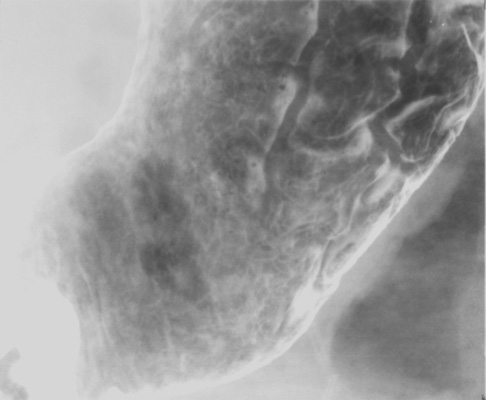

- Gastric antrum (patient LPO)